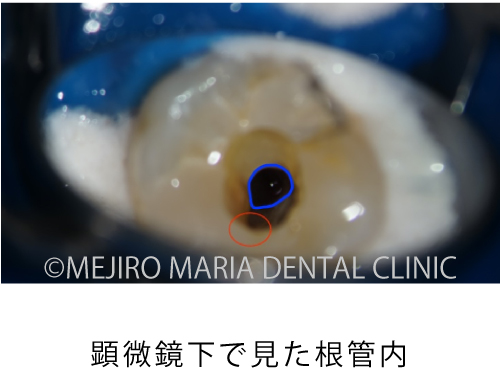

顕微鏡下で根管内を確認すると、レントゲン透過像通りに穴があいていること(穿孔)が確認され、実際の根管は治療が手つかずのままでした。

今回は根管形態が複雑ではなかったため、初回で根管内をすべて洗浄後、根管充填と穿孔修復(パーフォレーションリペア)を行い、2回目の治療にて、歯の土台を作る支台築造処置を終了させました。